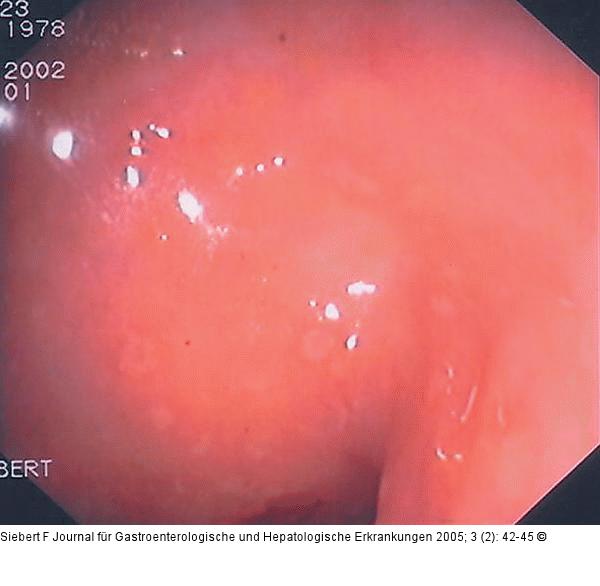

Abbildung 10a-f: Kolon - Reaktionsmuster Aphthen – Ischämisches Ulkus – Ödem, Hyperämie, Ulzeration – Zirkulär-ulzerös narbige Stenose – Pseudopolypös und narbig – Pseudomembranen (von oben nach unten) |

Abbildung 10c